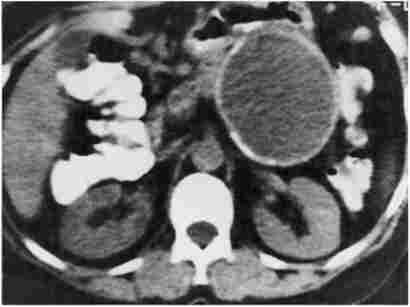

Цінним, хоча і більш дорогим методом діагностики панкреатичних кіст служить КТ, яка доповнює УЗД (рис. 20.17).

Комп'ютерна томографія

Мал. 20.17. Комп'ютерна томографія.

Псевдокиста підшлункової залози

Обидва ці методи допомагають диференціювати кистоподобную освіти ПЖ від кістозного або пухлинного ураження інших поруч розташованих органів, перш за все нирок і надниркових залоз. Під контролем УЗД або КТ здійснюється і діагностична пункція кіст через передню черевну стінку для дослідження їх вмісту (біохімічний аналіз, в тому числі на ферменти підшлункової залози; цитологічне дослідження осаду, мікробіологічне дослідження).